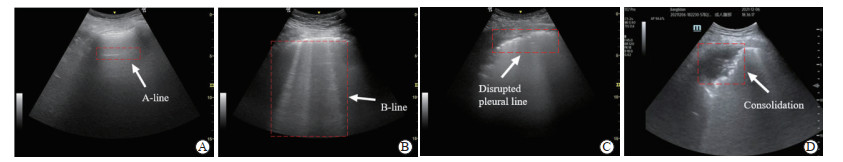

表 1 患者详细分布信息Table 1 Detailed distribution of patientsIndex Wuhan Huoshenshan Hospital N=31 The Second Affiliated Hospital of Naval Medical University N=28 Zhongshan Hospital of Fudan University N=10 Age/year, x±s 55±21 51±29 76±13 Gender, n Male 19 16 8 Female 12 12 2 Disease type Pneumonia Pneumonia/ARDS ARDS Imaging device LOGIQ e (GE HealthCare) M9 (Mindray HealthCare) M9 (Mindray HealthCare) ARDS: Acute respiratory distress syndrome. 用于评分任务的肺超声图像均由3名超声科医生(均具有6年以上超声诊断经验)依据国际肺超声共识[24]和临床诊断经验共同赋予对应的评分标签。评分过程中,先由2名医生独立评估图像,依据图像中的各类征象及典型病灶表现,将图像分为0分、1分、2分和3分4组,0分为正常,1~3分依次为病变程度由轻到重(图 1)。若2位医生的判断存在分歧,则由第3名医生进行最终判定。在此过程中,重叠、不清晰或存在伪影等质量不佳的图像均被剔除,并重新选取质量合格的图像予以补充。最终,从海军军医大学第二附属医院和武汉火神山医院获得5 000张肺超声图像,用于构建内部数据集(每个评分组1 250张)。其中,4 000张图像用于评分模型的训练与验证(每个评分组1 000张),1 000张图像用于内部测试(每个评分组250张)。此外,从复旦大学附属中山医院收集1 000张肺超声图像(0分:300张,1分:300张,2分:300张,3分:100张)作为外部测试集,用于评估模型在跨中心数据上的泛化能力。

图 1 4种不同评分的肺超声图像示意图Fig. 1 Representative lung ultrasound images with 4 different scoring levelsA: A-line (normal horizontal artifacts) indicating well-aerated lung (score 1); B: B-line (vertical artifacts) indicating interstitial syndrome (score 2); C: Disrupted pleural line indicating pleural discontinuity (score 3); D: Consolidation shows a tissue-like pattern with alveolar filling (score 4).1.2 轻量化肺超声图像定性评分

图 1 4种不同评分的肺超声图像示意图

Fig. 1 Representative lung ultrasound images with 4 different scoring levels

A: A-line (normal horizontal artifacts) indicating well-aerated lung (score 1); B: B-line (vertical artifacts) indicating interstitial syndrome (score 2); C: Disrupted pleural line indicating pleural discontinuity (score 3); D: Consolidation shows a tissue-like pattern with alveolar filling (score 4).